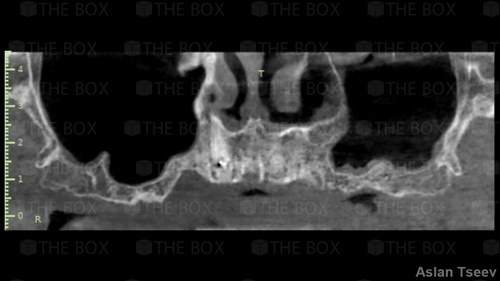

Infra bony defect one wall defect follow up 18 months show regeneration of buccal bone and interdental defect utilizing allograft bone substitute